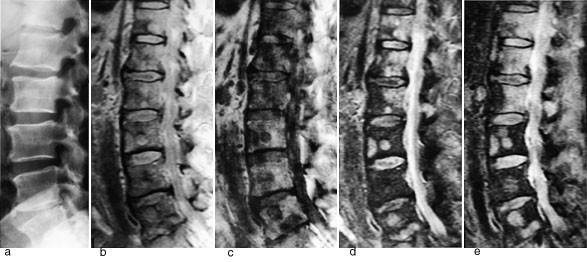

Figur 1 illustrerer det potensialet MR har til å påvise skjelettmetastaser. Protontetthetsbildet viser metastaser klart tydeligere enn det elektrontetthetsbaserte konvensjonelle røntgenbildet. Det T1-vektede bildet viser multiple metastaser med lavt signal, det T2-vektede bildet fremstiller metastasene med høyt signal. STIR (short inversion time inversion recovery)-bildet fremstiller også metastasene med høyt signal. På denne sekvensen summeres effekten av en lang T1 og en lang T2 (typisk for tumor), samtidig med at signalet fra fett er undertrykt. Dette gir sekvensen meget høy sensitivitet.

Ved truende og manifeste tverrsnittslesjoner hos kreftpasienter vil årsaken oftest være skjelettmetastaser med omgivende intraspinal, ekstradural bløtdelstumor som komprimerer medulla. Minst 20 % av pasientene vil ha medullakompresjon på mer enn ett sted (6). Hele columna bør undersøkes. MR viser både metastasene og medullakompresjonen, og MR-undersøkelse er den beste metoden til å utrede disse pasientene. Sagittale T1-sekvenser og STIR- eller T2-sekvenser gir god oversikt over medulla (fig 2), og kan eventuelt suppleres med aksiale snitt svarende til medullakompresjonen. I en artikkel i Tidsskriftet har Brenne og medarbeidere gitt en utførlig omtale av medullakompresjon ved metastatisk kreftsykdom (7). Vi slutter oss til det syn at utredningen bør skje raskt, ved hjelp av MR. Det er viktig å være oppmerksom på at de aller fleste pasienter med medullakompresjon har hatt utstrålende radikulære smerter i nivå for kompresjonen i forkant av de nevrologiske utfall.